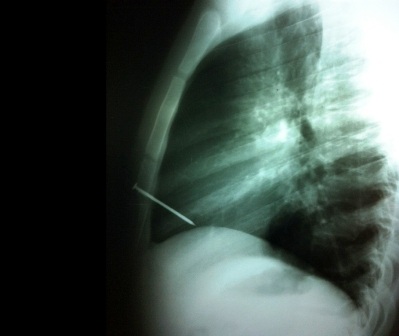

Sau khi được đưa tới bệnh viện, các bác sĩ đã tiến hành chụp X-quang và phát hiện thấy chiếc đinh trên bắn trúng khu vực khoang tim. Bệnh nhân sau đó đã được phẫu thuật để lấy chiếc đinh ra. Ca phẫu thuật nguy hiểm kéo dài hơn 2 tiếng đồng hồ.

Ảnh X-Quang cho thấy chiếc đinh đâm thẳng vào khoang tim